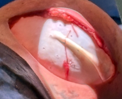

Adult female underwent nipple-sparing mastectomy with bilateral IBR using implants and ADM. Robotic-assisted nerve coaptation performed using Symani with 11-0 suture on ~0.4mm nerves. Autograft from 4th/5th medial nerve used. Sensation expected to return in 3 months.